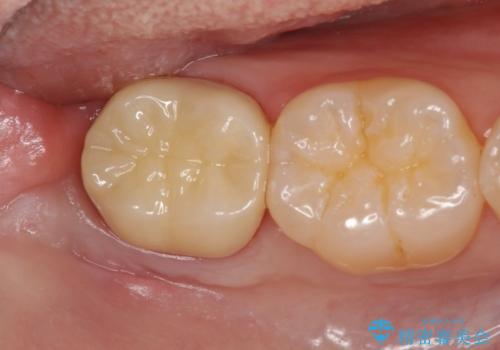

親知らずを起因とする虫歯治療

親知らずは抜去を行い、手前の第2大臼歯は根管治療後セラミッククラウンの製作を行います。

- 20万円(大臼歯根管治療・仮歯・ファイバーコア・フルジルコニアクラウン)費用は治療当時の料金となります